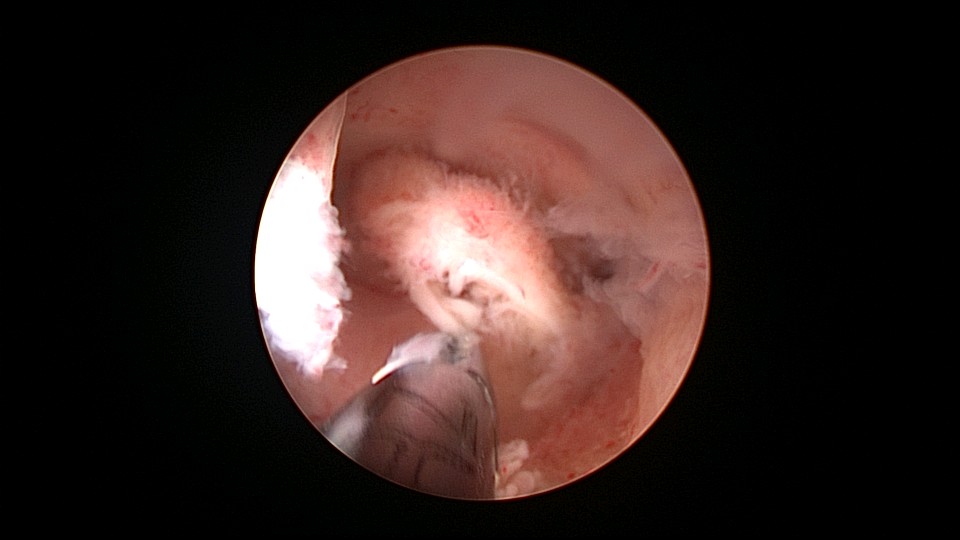

患者38岁,G2P1,剖宫产1次。安环13年,发现内膜息肉3年伴月经淋漓不净。2025年3月行宫腔镜取环、息肉切除,同时放置曼月乐环并固定。子宫后位,宫深7.5cm,宫型环位置正常,宫颈管及宫腔后壁见息肉,顺利取出节育环,切除息肉送病检,4-0不可吸收线将曼月乐缝合固定于宫腔上段后壁,第一次做宫腔镜下缝合固定节育环,体外打结后推结到位比较困难,今后改进缝合固定方式。病检为子宫内膜息肉及增殖期子宫内膜。2025年4月复查B超,曼月乐位置正常,环顶端距宫底1.3cm。